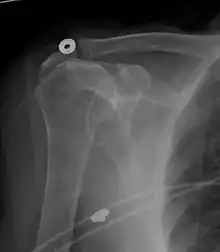

Diagnostic modalities, dependent on circumstances, include X-ray, MRI, MR arthrography, double-contrast arthrography, and ultrasound. Although MR arthrography is currently considered the gold standard, ultrasound may be most cost-effective.[34] Usually, a tear will be undetected by X-ray, although bone spurs, which can impinge upon the rotator cuff tendons, may be visible.[35] Such spurs suggest chronic severe rotator cuff disease. Double-contrast arthrography involves injecting contrast dye into the shoulder joint to detect leakage out of the injured rotator cuff,[36] and its value is influenced by the experience of the operator. The most common diagnostic tool is magnetic resonance imaging (MRI), which can sometimes indicate the size of the tear, as well as its location within the tendon. Furthermore, MRI enables the detection or exclusion of complete rotator cuff tears with reasonable accuracy and is also suitable for diagnosing other pathologies of the shoulder joint.[37]

MRI

Magnetic resonance imaging (MRI) and ultrasound[46] are comparable in efficacy and helpful in diagnosis, although both have a false positive rate of 15–20%.[47] MRI can reliably detect most full-thickness tears, although very small pinpoint tears may be missed. In such situations, an MRI combined with an injection of contrast material, an MR-arthrogram, may help to confirm the diagnosis. It should be realized that a normal MRI cannot fully rule out a small tear (a false negative) while partial-thickness tears are not as reliably detected.[48] While MRI is sensitive in identifying tendon degeneration (tendinopathy), it may not reliably distinguish between a degenerative tendon and a partially torn tendon. Again, magnetic resonance arthrography can improve the differentiation.[48] An overall sensitivity of 91% (9% false negative rate) has been reported, indicating that magnetic resonance arthrography is reliable in the detection of partial-thickness rotator cuff tears.[48] However, its routine use is not advised, since it involves entering the joint with a needle, with the potential risk of infection. Consequently, the test is reserved for cases in which the diagnosis remains unclear.